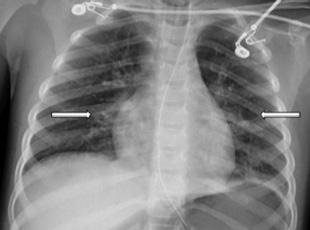

On arrival, the patient was tachypneic (respiratory rate of 27 breaths per minute) and coughing, and appeared to be in distress. She had coarse breath sounds and a room air oxygen saturation of 88% (reference range 95-100%). She was placed on heated high-flow nasal cannula delivering 40% oxygen at 16 liters per minute (L/min), which initially increased her oxygen saturation to 99%. A chest radiograph (CXR) was obtained and interpreted as unremarkable. An initial venous blood gas (VBG) revealed a partial pressure of carbon dioxide (pCO2) of 29 millimeters of mercury (mm Hg) (35-45 mm Hg) with pH 7.39 (7.35-7.45). While in the ED, her respiratory rate increased to 36 breaths per minute, her mental status declined, and she developed diffuse crackles on chest auscultation. A repeat VBG 65 minutes after arrival (45 minutes after initial VBG) revealed pCO2 of 58 mm Hg with pH of 7.22.

With obtundation and a worsening respiratory acidosis, she was intubated and placed on synchronized intermittent mandatory ventilation with a fraction of inspired oxygen (FiO2) of 75% and positive end-expiratory pressure of 7 mm Hg. A post-intubation CXR, performed approximately

148 minutes after arrival (98 minutes after the initial CXR), revealed bilateral patchy perihilar and peribronchial opacities (Image 2). There were no acute complications with the intubation, and the patient remained hemodynamically stable while being transferred to the intensive care unit (ICU).

In the ICU she received continued mechanical respiratory support and intermittent diuresis with furosemide to maintain neutral fluid balance. The infiltrates seen on CXR worsened over the next three days with progression of mixed interstitial

and alveolar opacities (Image 3). Despite a worsening CXR appearance, the patient maintained adequate oxygenation with ventilator settings of FiO2 of 30% and positive endexpiratory pressure of 5 mm Hg. She had intermittent fevers and leukocytosis, with a maximum white blood cell count of 26 x 103 cells per microliter (μL) (reference range 4.5 x 103 - 11 x 103 cells/μL); however, antibiotics were deferred. There was no evidence of extrapulmonary organ damage on clinical exam or laboratory testing throughout the duration of her hospitalization. Two respiratory pathogen panels testing for 22 pathogens obtained on hospital days (HD) 2 and 4 were negative, as were blood, urine, and sputum cultures. She was extubated on HD 5. Post-extubation, she required 35-40% FiO2 via heated high-flow nasal cannula at 8-10 L/min for an additional two days as her CXR improved. She required supplemental oxygen until HD 9 and was discharged home the following day.

Chest radiograph on hospital day three showing worsening bilateral infiltrates and progression of mixed interstitial and alveolar opacities